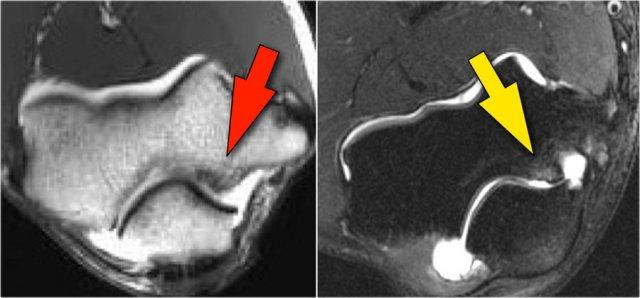

Do quá tải valgus, có các lực cắt tác động lên phần sau-trong của khớp cánh tay-trụ.

Lưu ý tình trạng xơ cứng dưới sụn được thấy trên ảnh T1W (mũi tên đỏ).

Trên hình ảnh T2W có phù tủy xương dưới sụn và mất sụn khớp (mũi tên vàng).

Đây là hình ảnh của một vận động viên bóng chày 20 tuổi.